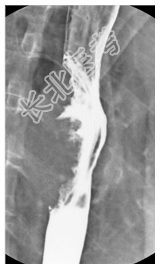

- [材料题] 病历摘要:男,70岁。因剑突下疼痛伴吞咽异物感2月来诊。查体:无特殊。给予食道吞钡检查。

- 简答题1、诊断及依据是什么?

- 简答题2、鉴别诊断有哪些?